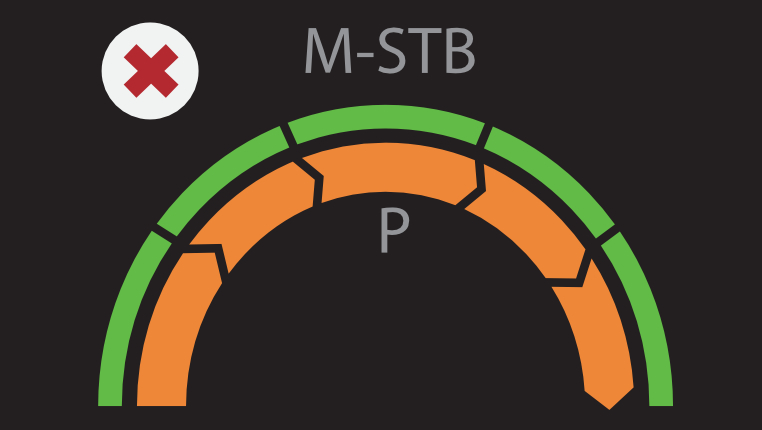

? ??? ?? ???? ???? ?? ???? Hepatus? ? ??? ??? ???? ??? ??? ?????. ???? ????? ??? ? ?? ??? ???? ????? ? ?? ???? ? ?? ??? ??? ??? ?????.

??? ???? ?? ? ??? ? ? ???? ?? ??, ??, ???? ? ?? ??? ??? ? ????. ?? ?? ???? ?????.